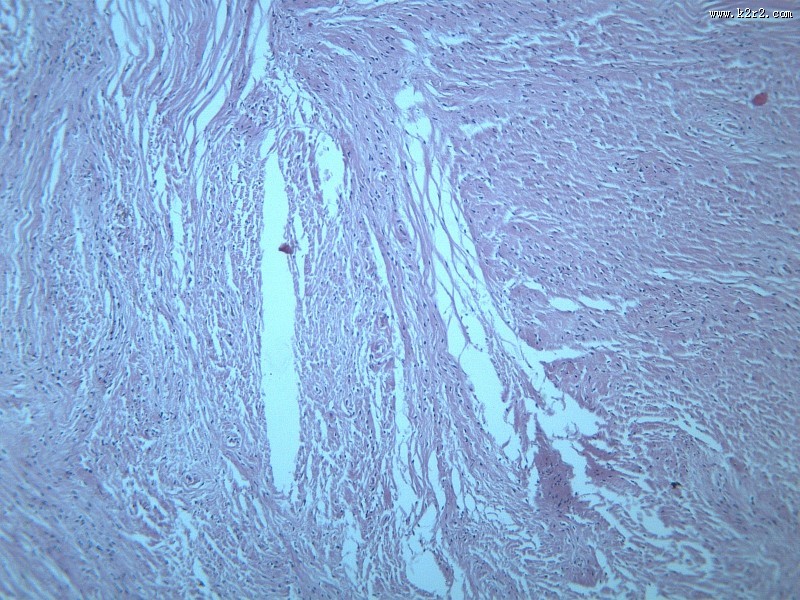

纤维瘤大全 - 第10张

纤维瘤大全

图集中 / 共有 12 张图片

乳腺纤维腺瘤

纤维肉瘤大全

医学

显微切片

肿瘤

fibroma

纤维瘤